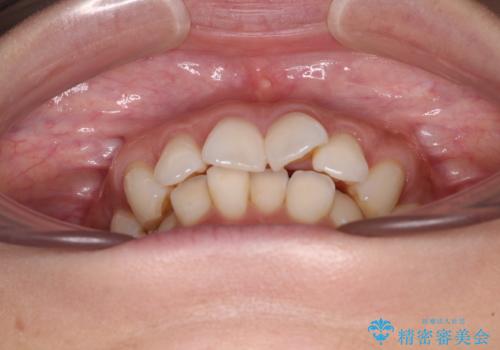

- 前歯の突出感とデコボコを気にして来院された患者様です。

奥歯の噛み合わせをみると、上顎歯列が全体的に前突している状態であり、この咬み合わせのまま歯列を整えると出っ歯になってしまう可能性がありました。

アンカースクリューと補助装置を使用して上顎大臼歯を遠心移動させることで咬み合わせを改善し、ワイヤー装置によりデコボコを解消しながら口元の突出感も改善していくこととしました。